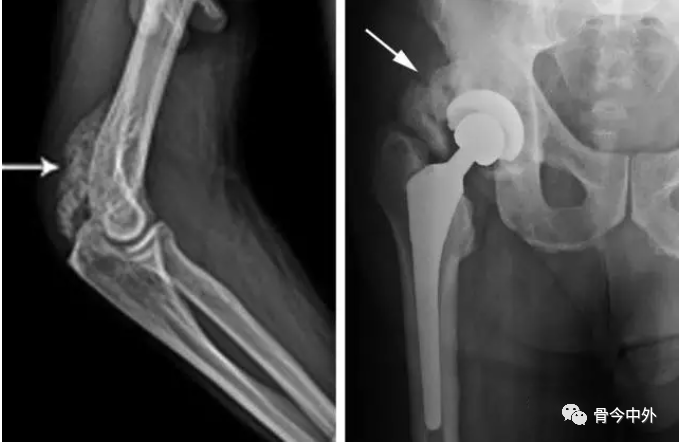

关于HO的发生率,多数研究报道为10%~20%。无论是中枢神经损伤性还是四肢创伤性HO,最好发是髋关节,其次是肘、膝、肩,几乎不累及腕、踝、手、足这样的小关节。

脊髓损伤患者的HO极少发生于上肢关节。创伤性HO可位于关节旁或将关节包绕,而神经损伤性HO则往往位于关节旁。在创伤骨科中,尤以髋臼骨折和肘关节骨折最为多见。关节置换术后以及严重的长骨骨折后异位骨化发病率为3%~20%。

髋臼骨折和肘部骨折所致异位骨化最为常见,髋臼骨折内固定术后大约40%患者形成异位骨化。Guo等推荐髋臼骨折手术采用粗隆翻转或者后侧入路,异位骨化在粗隆翻转、前路手术及后路手术的发生率分别为33.3%、42.1%和36.9%